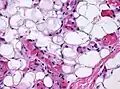

.jpg.webp) Small vessels in adipose tissue

Small vessels in adipose tissue.jpg.webp) Small vessels in adipose tissue

Small vessels in adipose tissue Small vessels in adipose tissue

Small vessels in adipose tissue Small vessels in adipose tissue

Small vessels in adipose tissue The vessels typically contain hyaline or fibrin (pictured) thrombi[4]

The vessels typically contain hyaline or fibrin (pictured) thrombi[4]